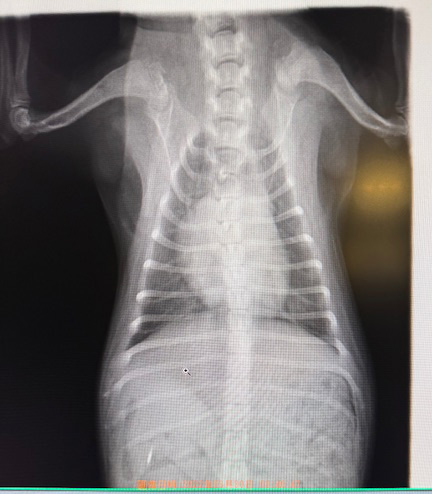

• 必要に応じて、レントゲン検査にて気管支炎や肺炎の有無を、血液検査にて炎症の程度(白血球数、CRP)を評価します。